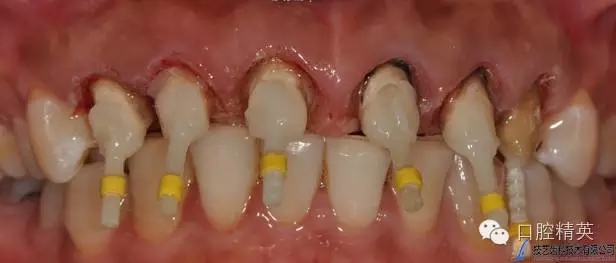

PD纖維樁樹脂修復(fù)

水激光切除牙齦

臨時(shí)冠修復(fù)